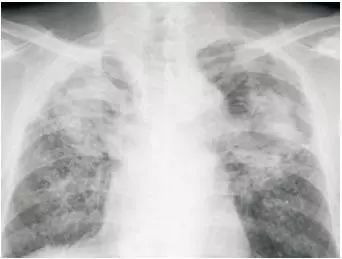

X 光检查就像给身体拍一张平面照片。它利用 X 射线穿透人体,不同组织对 X 射线吸收程度不同,从而在胶片或探测器上形成黑白影像。骨骼含钙量高,吸收 X 射线多,在片子上显示为白色;而含气的肺部吸收 X 射线少,呈现黑色。

这种检查价格亲民,成像速度快,1 分钟左右就能拿到结果,是骨科和胸部疾病初步筛查的常用手段。比如怀疑骨折时,X 光片能快速发现骨头是否断裂、错位;检查肺部时,也能清晰显示肺部的大体形态,判断是否有肺炎、气胸等问题。但由于 X 光只能呈现二维平面图像,前后组织会相互重叠,细微病变或复杂部位的情况可能难以准确判断。

- 胸部不适:胸部 X 光可作为初步筛查手段,观察肺部大致形态。但对于早期肺癌筛查,胸部 CT 更为精准,能发现毫米级的肺小结节,帮助医生早发现、早诊断。